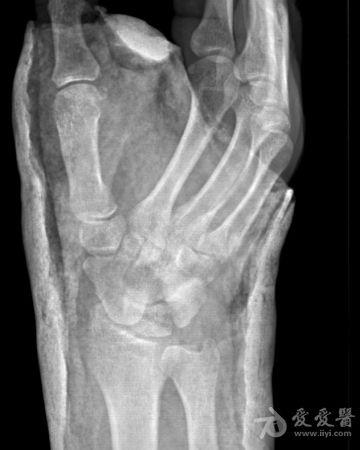

右手舟状骨骨折4个月

右手舟状骨骨折四个月,一直石膏保守治疗,拍片如下,请问,现在是手术治疗好还是继续保守治疗?